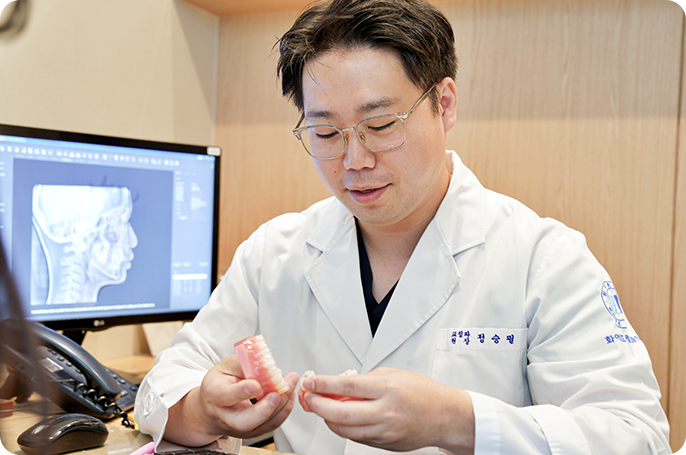

임플란트

디오임플란트

높은 기술력과 브랜드 신뢰도

오스템임플란트

국내판매 1위 브랜드

덴티움임플란트

해외 수출 국제 인증 브랜드